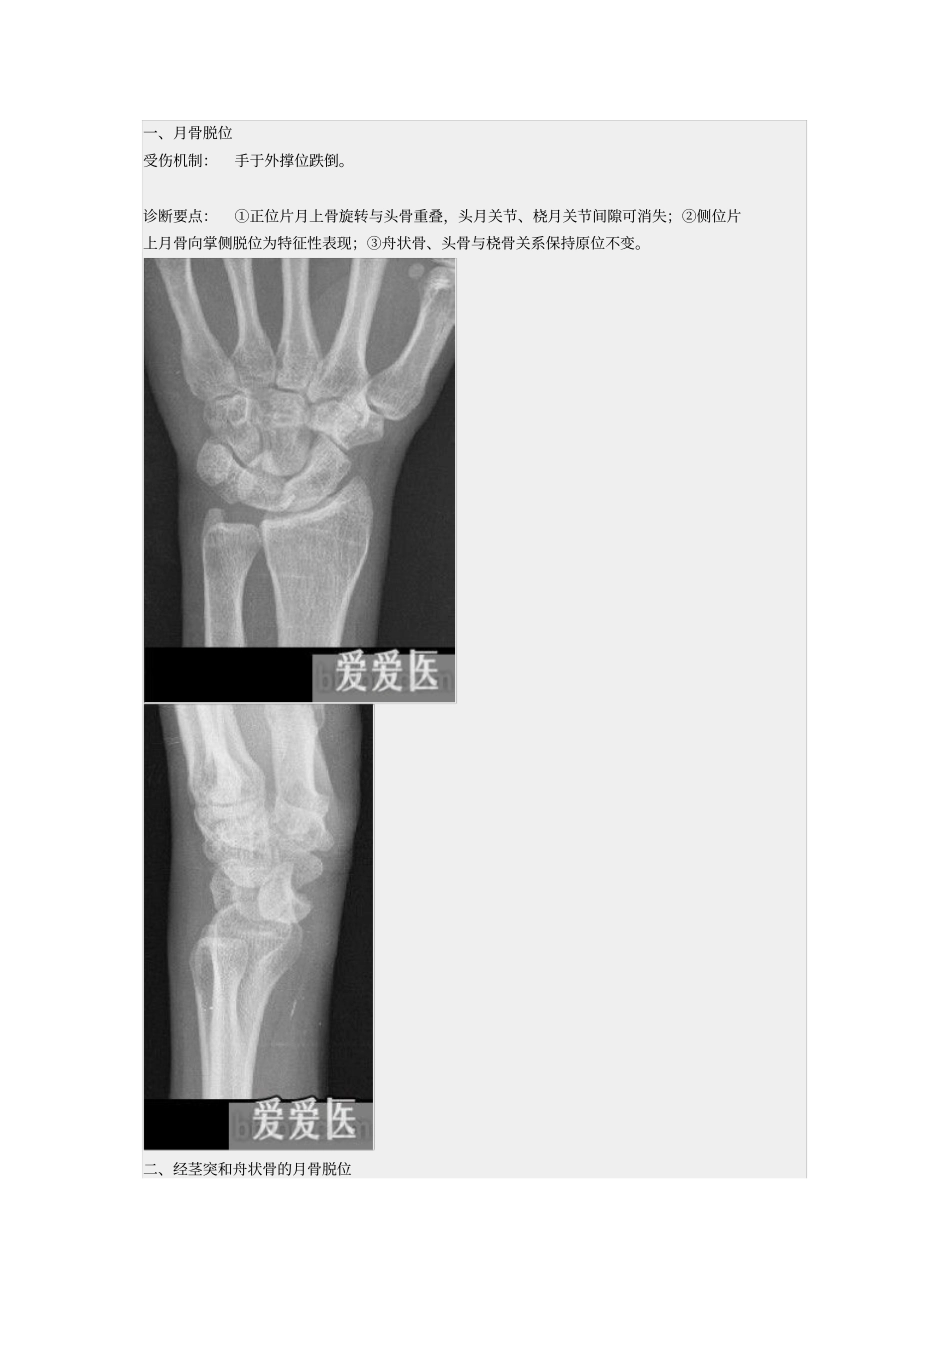

一、月骨脱位受伤机制:手于外撑位跌倒。诊断要点:①正位片月上骨旋转与头骨重叠,头月关节、桡月关节间隙可消失;②侧位片上月骨向掌侧脱位为特征性表现;③舟状骨、头骨与桡骨关系保持原位不变。二、经茎突和舟状骨的月骨脱位受伤机制:手于外撑位跌倒,腕过度背伸。诊断要点:①尺骨或桡骨茎突骨折;②舟状骨中段骨折,近端与头骨重叠;③月骨可向尺侧移位,月骨窝状关节空虚,对向掌侧;④头骨位于月骨后方。三、月骨周围脱位受伤机制:摔倒时手背伸、尺偏和旋前位着地,发生月骨周围脱位。临床表现:腕部肿胀向背侧突出,屈伸活动受限,局部疼痛、压痛。诊断要点:①正位片上头月骨重叠,关节间隙出现消失或变窄;②侧位片上月骨原位不动,桡月关节正常, 月骨上关节面空虚;③头状骨位于月骨背侧缘的后上方;④舟状骨向背侧脱位;⑤可伴有桡骨背缘骨折。四、经舟状骨月骨周围脱位受伤机制:摔倒时手背伸、尺偏和旋前位着地,发生月骨周围脱位。诊断要点:①舟状骨骨折;②正位片上头月关节间隙异常;③侧位片上月骨原位不动,舟状骨近侧骨折块和月骨与桡骨的关系正常,月骨上关节面空虚;④头状骨位于月骨背侧缘的后上方。五、经茎突和舟状骨的月骨周围脱位受伤机制:跌倒时手掌着地,腕过度背伸。诊断要点:①尺、桡骨茎突骨折;②舟状骨中段骨折,近端与头骨重叠;③月骨可向尺侧移位,月骨窝状关节空虚;④头骨位于月骨后方;⑤月骨和舟状骨近端与桡骨关节可正常或向掌侧半脱位。六、三角骨月骨周围脱位受伤机制: 本病的主要表现与月骨周围脱位相似,只是三角骨与钩骨关节间的脱位取代了三角骨与月骨关节间脱位。诊断要点:①月骨、三角骨及桡骨三者关系正常;②其余腕骨向背侧脱位。七、舟状骨脱位受伤机制:舟状骨有旋转性半脱位与全脱位两种类型,两者受伤机制完全不同。前者系中腕关节移位时致舟状骨近端发生旋转性半脱位,较常见;而舟状骨全脱位为直接暴力所致,非常罕见。诊断要点:腕部症状多较严重,有时可伴有神经受压症状。脱出的舟状骨位于皮下,可触及。八、小多角骨脱位受伤机制: 小多角骨脱位较罕见,可为单独脱位,或合并邻近骨的骨折或脱位,脱位的小多角骨多脱向背侧。